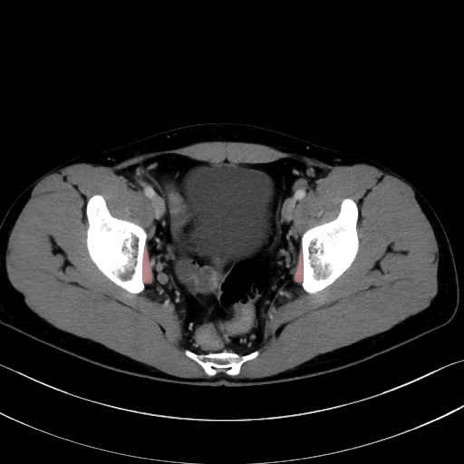

内閉鎖筋(obturator internus) のCT画像の解剖

内閉鎖筋 (Obturator internus)